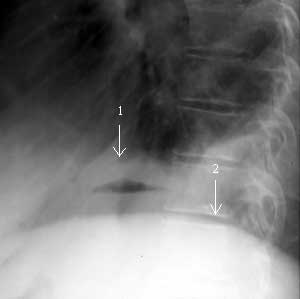

Рис. 6. Левая боковая рентгенограмма грудной клетки. Под правым куполом диафрагмы имеется уровень жидкость-газ (абсцесс). 1 - правый купол диафрагмы, 2 - левый купол.